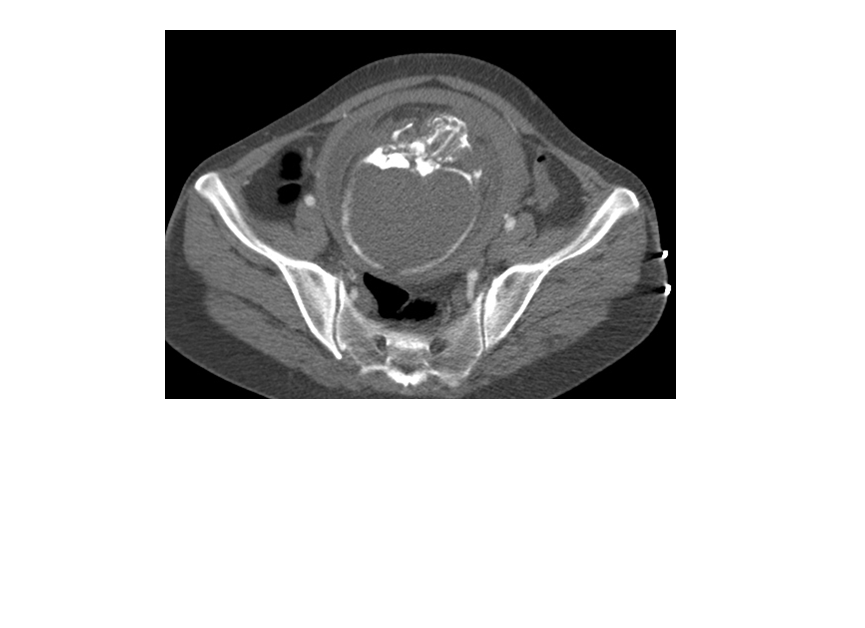

CT表现:自主动脉根部起至腹主动脉肾动脉水平可见撕裂之动脉内膜瓣影,子宫腔内可见胎儿影。

诊断结果:妊娠合并主动脉夹层(I型)。

1、撕裂的内膜瓣:多表现为弯曲的线样低密度影,部分患者可见多个破口,内膜漂浮在管腔中。

3、真、假腔的显示:真假腔可同时显影,或假腔强化和排空比真腔延迟;假腔内常有血栓形成可呈略高密度影,当多个破口存在时,真假腔较难区分。一般情况下假腔较大,真腔较小。